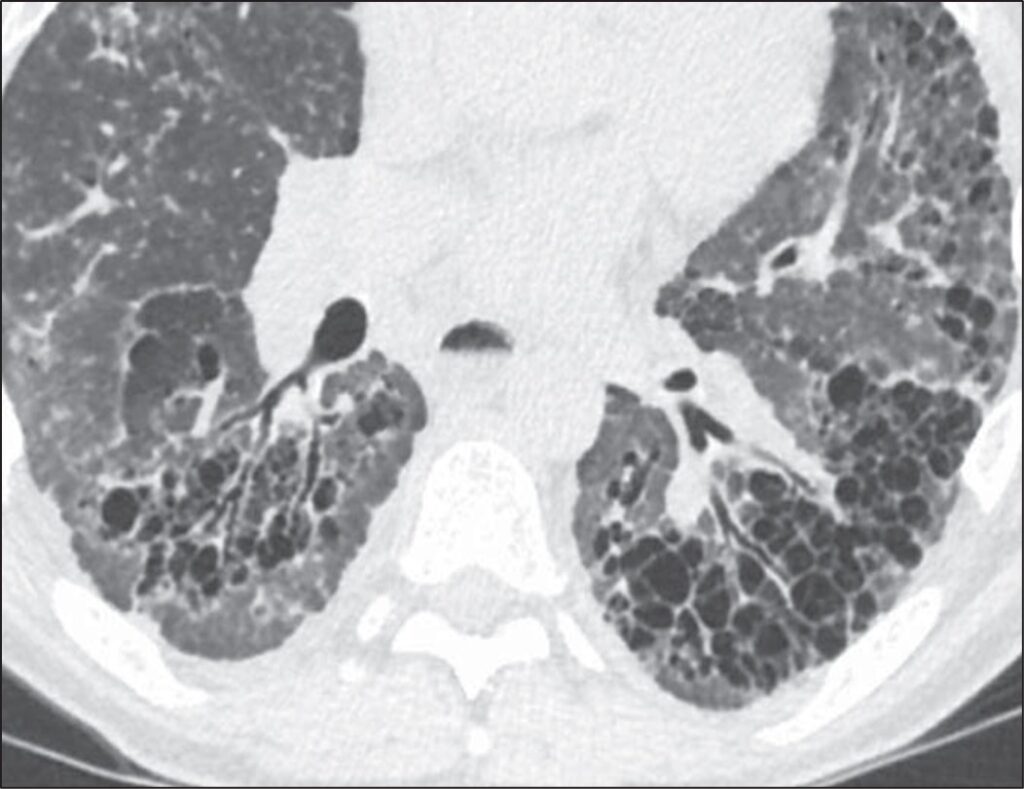

Honeycombing can be confidently diagnosed when there is a group of round clustered air-filled cysts in a row or cluster in the subpleural lung [5]. The subpleural involvement in honeycombing is critical in distinguishing it from other abnormalities. Multiple layers of cysts increase the reader’s confidence in honeycombing but are not required for diagnosis. Honeycomb cysts usually range in size from 3 to 10 mm and have relatively thick, well-defined walls [6]. In general, there is moderate agreement among radiologists for the presence of honeycombing, with kappa values ranging from 0.4 to 0.6 in one series comparing 43 different observers. There was disagreement on the presence of honeycombing in 29% of these cases [7]. Use of the above general rules for the features of honeycombing is helpful when distinguishing from common mimics. The most frequent findings mistaken for honeycombing include traction bronchiectasis, cystic lung disease, emphysema, and subpleural reticulation [8].To distinguish traction bronchiectasis from honeycombing, the shape of the air-filled structure should be noted. Airways in traction bronchiectasis are tubular in shape, which may be best seen on multiplanar reformatted images. Additionally, air-filled structures in the central or peribronchovascular lung are not consistent with honeycombing and are very likely a result of dilated airways (Fig. 2).

Fig. 2—Patient with scleroderma and fibrotic nonspecific interstitial pneumonia. Left, HRCT scan shows traction bronchiectasis mimicking honeycombing. Right, HRCT scan shows that air-filled structures spare subpleural lung.